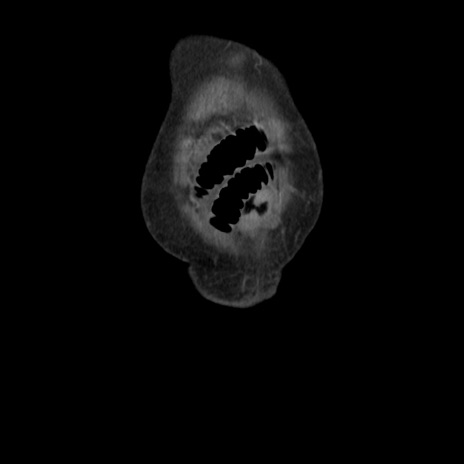

横断像

【症例】80歳代 女性

【主訴】腹部膨満感

【現病歴】他院にて肝硬変にてフォロー中。1週間前から便秘、腹部膨満感、臍部腫瘤あり受診となる。

【既往歴】肝硬変

【身体所見】腹部膨隆あり、皮膚変化なし、疼痛なし。

【データ】WBC 4600、CRP 0.25